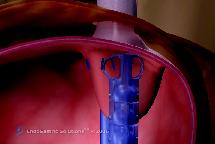

Η ανάγκη για μιά νέα μέθοδο αντιμετώπισης της ΓΟΠΝ, ισάξιας αποτελεσματικότητας με την Nissen αλλά χωρίς τους περιορισμούς και τα προβλήματα της, οδήγησε στη δημιουργία διαφόρων ενδοσκοπικών μεθόδων, οι οποίες στην πλειοψηφία τους απέτυχαν. Εξαίρεση αποτελεί η διαστοματική θολοπλαστική EsophyX. Η μέθοδος EsophyX είναι μία χειρουργική τεχνική όπου η γαστροοισοφαγική βαλβίδα διορθώνεται από το εσωτερικό του στομάχου. Με χρήση γενικής αναισθησίας η συσκευή εισάγεται από το στόμα (εικ.1), με την βοήθεια γαστροσκοπίου, και φθάνει στο στομάχι ενδοαυλικά (εικ.2). Με ανάστροφη όραση γίνεται συρραφή και επανακατασκευή της γαστροοισοφαγικής συμβολής με ειδικά clips που τοποθετούνται σε όλο το πάχος του τοιχώματος του στομάχου (εικ.3). Όταν υπάρχει μικρή διαφραγματοκήλη ανατάσσεται με την εισαγωγή και τοποθέτηση του οργάνου.

Εικόνα 2: Με την βοήθεια γαστροσκοπίου φθάνει στο στομάχι ενδοαυλικά.